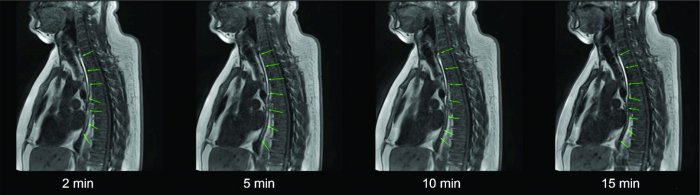

The drug delivery principle’s functionality was demonstrated via MRI (magnetic resonance imaging), using the fully developed device loaded with a contrast agent. The trial showed that it is possible to deliver a mucoadhesive film to the esophagus by rolling off from a capsule during swallowing. It was found that the film rolled off in all healthy volunteers participating in the study and was correctly placed and attached to the esophageal mucosa in each single case. MRI images were generated at different time points after application. It was determined that the film is visible on the esophageal mucosa for at least 15 minutes. This is significantly longer than the contact time of less than one minute for oral orodispersible tablets (Burton et al., 1995; Washington et al., 2000). The general swallowability and acceptance were very good and no severe reactions (e.g. vomiting) were observed.